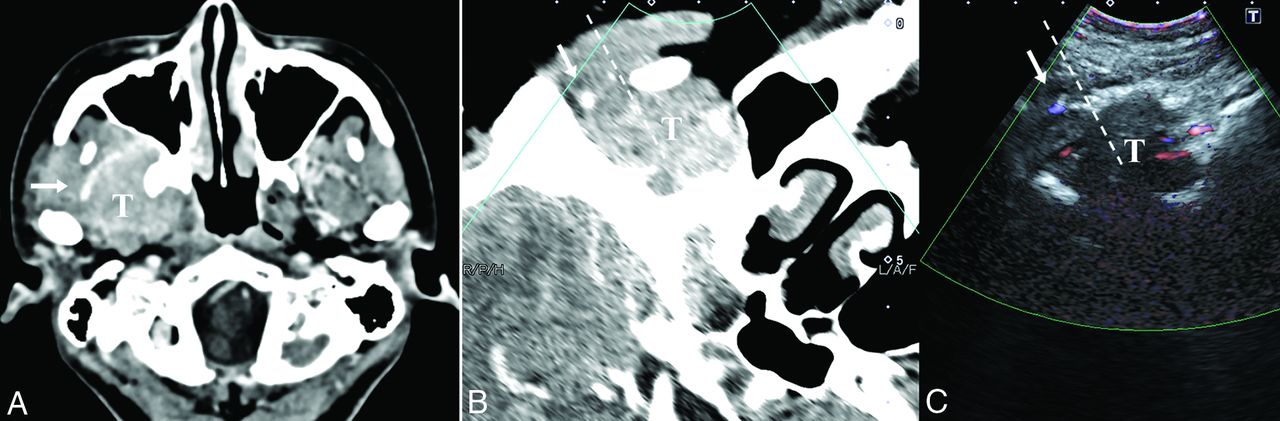

A 58-year-old woman without clinical presentation (patient No. 2). A, Axial T1-weighted postcontrast MR image shows a left parapharyngeal lesion with heterogeneous hyperintensity and a demarcated border. The target lesion is located deep in the parotid gland, and the ICA (arrow) is displaced medially. After a successful fusion of MR imaging (B) and US (C), MR imaging facilitates the accurate localization of the target lesion, which is ill-defined on US, with the ICA (arrow) confirmed on the color Doppler mode and the overlay mode (yellow mask). The dotted line indicates the expected needle path via the retromandibular approach. The histopathologic yield was schwannoma. T indicates target lesion; PG, parotid gland.